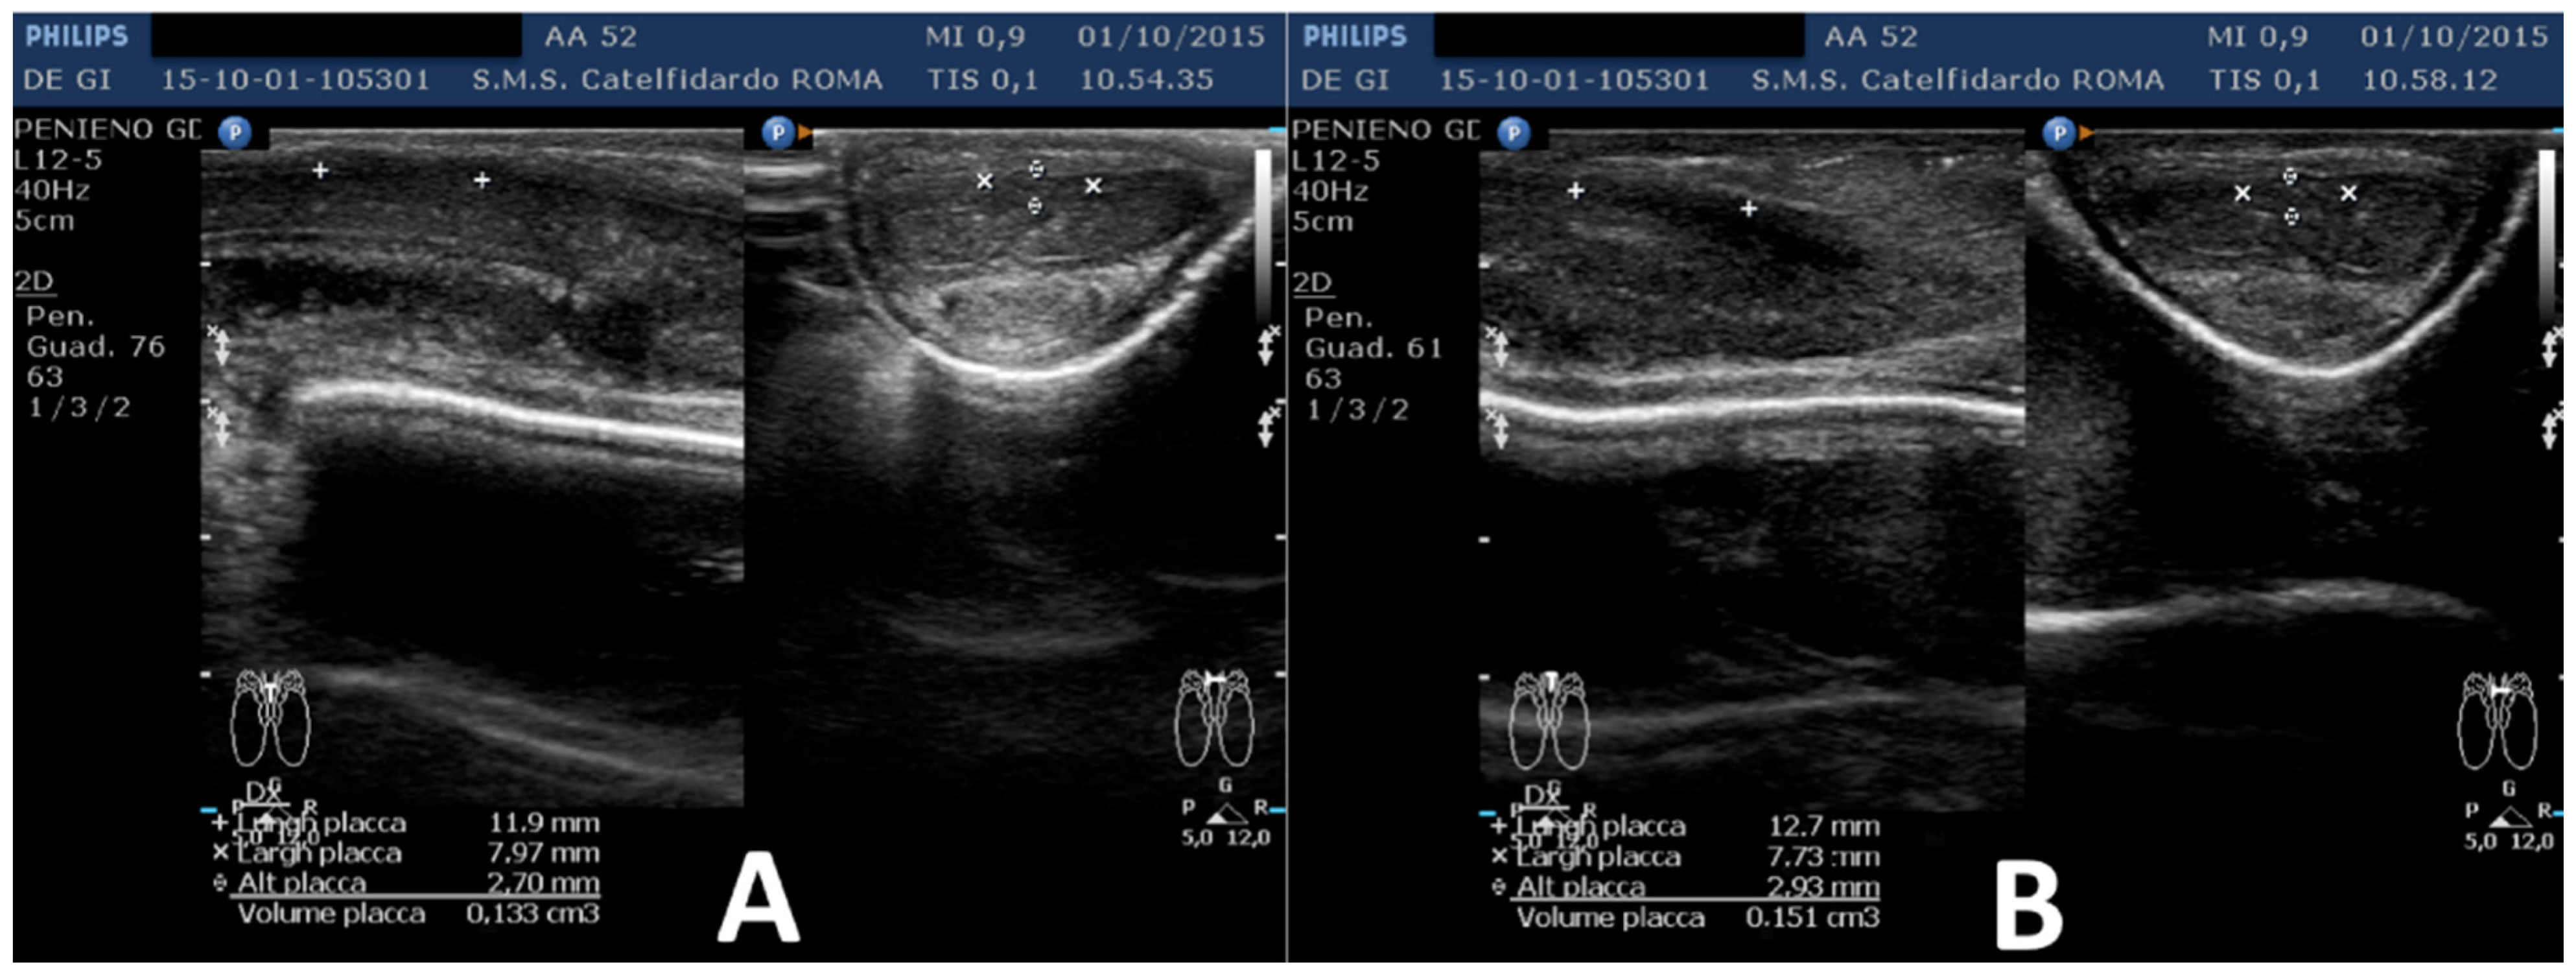

| 2 | 52 years | Dupuytren’s disease, Ledderhose disease, congenital dorsal penile curvature (5 degrees). | Middle third + distal third | (A) First plaque: 13.4 × 9.15 × 2.83 mm volume = 182 mm3. Second plaque: 14.8 × 8.43 × 3.87 mm. Total volume = 252 mm3 (B) No plaque detected | (A) 20-degree dorsal penile curvature + 20-degree left penile curvature (B) 5-degree dorsal penile curvature. Previous condition = congenital dorsal penile curvature (5 degrees) | VAS score = 0 | 26 > 27 | 51 months | Orally: propolis 600 mg + bilberry 160 mg + silymarin 400 mg + ginkgo biloba 250 mg + L-carnitine 1000 mg + coenzyme Q10 100 mg + Boswellia 200 mg + vitamin E 30 mg/daily for 51 months + topically: diclofenac gel 4%/2× daily for 51 months + periplaque penile injections: pentoxifylline 100 mg (30 G needle) every 2 weeks for 6 months, and then 1 penile injection every month for 12 months, and 1 penile injection every 2 months for 24 months (42 total injections) |